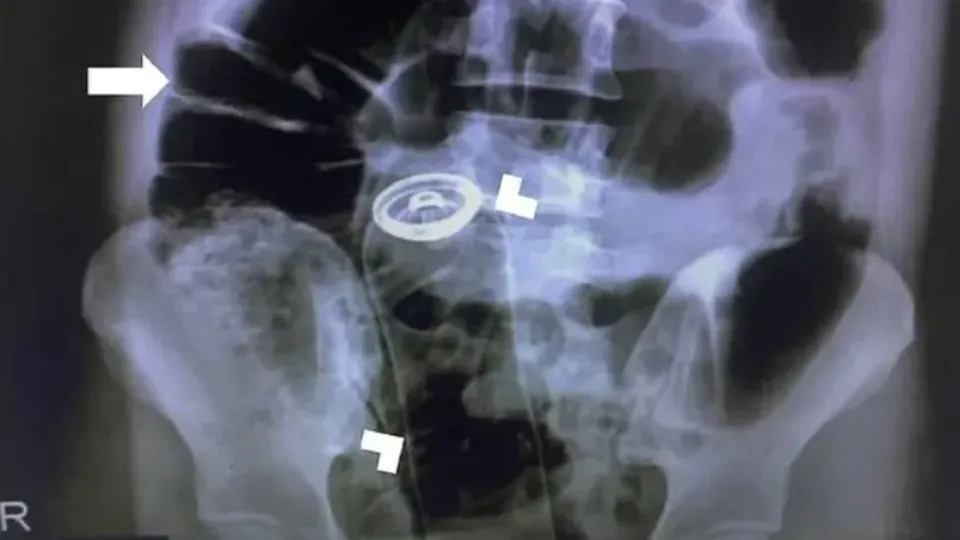

Paciente contou que não conseguia tirar o objeto e sentia dores fortes

Um homem precisou de atendimento médico no Hospital João Paulo II, em Porto Velho (RO), ao introduzir um frasco de desodorante no reto. O caso ocorreu na última quarta-feira (12).

Conforme informações obtidas pelo Portal SGC, o homem chegou no Hospital João Paulo II e contou que estava sentindo dores fortes na barriga. Logo em seguida, ele contou que introduziu um frasco de desodorante no reto e não conseguiu tirar.

Então, a equipe realizou os procedimentos de praxe para fazer a remoção do objeto. Logo em seguida, o homem foi submetido a um procedimento cirúrgico para a retirada do frasco. O hospital não divulgou o estado de saúde do paciente. sgc

Foto Ilustrativa